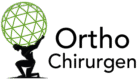

Röntgenbild einer inversen Schulterprothese: Die natürliche Anordnung von Gelenkkopf und Gelenkpfanne wird umgekehrt.